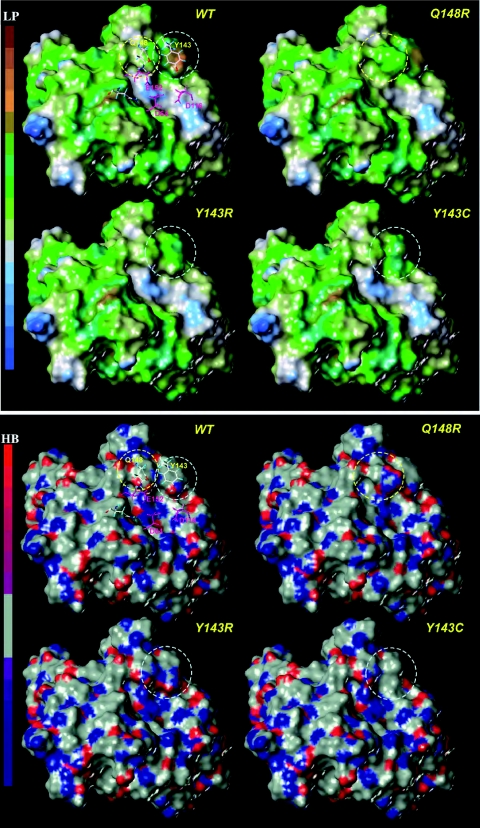

We previously demonstrated that the Q148R/H/K mutation alters the specificity of DNA recognition by IN (31). We thus compared the hydrophobicity and hydrogen-bonding patterns of the WT and mutant proteins, both factors playing key roles in the binding of substrates or inhibitors. To compare the contributions of residues Y143R/C and Q148R in modulating the target binding properties and their roles in the complex formation with substrate (DNA) or RAL, we generated the molecular Connolly and MOLCAD surfaces for the WT and mutant INs and analyzed the lipophilic potential (LP) and hydrogen bonding (HB) properties. Lipophilicities of the Y143R/C and Q148R mutants were similar, whereas LP on the IN surface in mutants was considerably lower than that in the WT enzyme (Fig. 7, top). Therefore, a reduced capability to stabilize inhibitors through nonspecific hydrophobic interaction in the vicinity of these residues is expected. The analysis of hydrogen bonding sites on the IN surface also highlighted significant changes to the donor/acceptor properties of the mutants in comparison with those of the WT enzyme (Fig. 7, bottom). In particular, both mutations Q148R and Y143R/C contributed to form a pure hydrogen donor site instead of the mixed donor/acceptor binding sites observed in the context of the wild-type enzyme (Fig. 8A).

FIG. 7.

Lipophilic potential (LP) (top) and hydrogen bonding site (HB) (bottom) surfaces of wild-type and raltegravir-resistant mutants. LP and HB calculations performed on the Connolly solvent-accessible surface of the INs were determined using the MOLCADE subroutine from SYBYL 8.0 (Tripos Inc., St Louis, MO). The color ramp for LP ranges from brown spots (highest lipophilic potential area of the molecule) to blue spots (highest hydrophilic area). The color ramp for HB ranges from red (hydrogen donors; low electronegativity) to blue (hydrogen acceptors; high electronegativity). The RAL-resistant and catalytic residues are shown as sticks and in magenta, respectively. The areas corresponding to the RAL resistance mutations on the IN surface are delimited by dashed circles, yellow for Q148R and Y143R/C and blue for N155H.